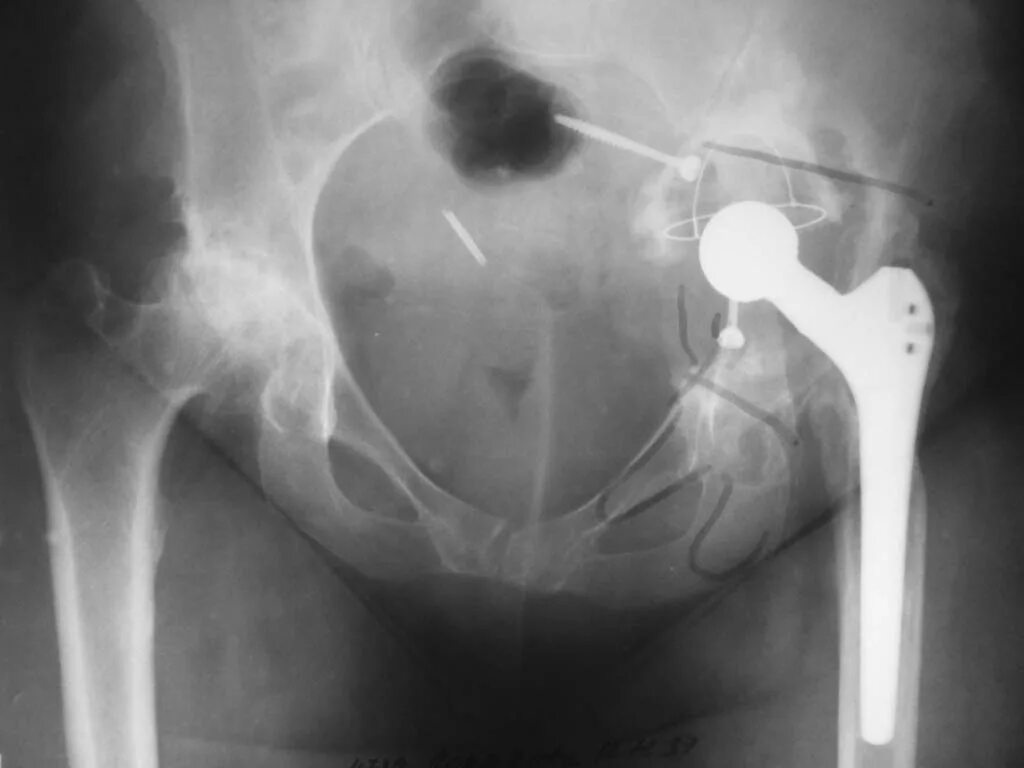

Замена тазобедренного сустава наркоз